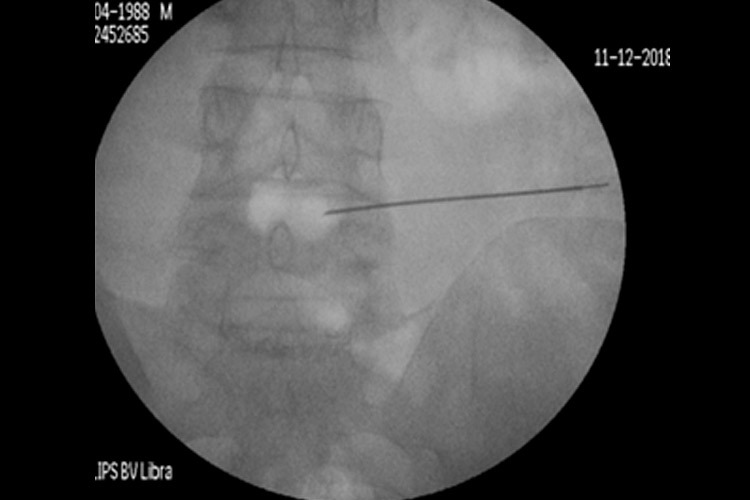

Με τον δεύτερο τρόπο γίνεται, υπό ακτινοσκοπικό έλεγχο, διαδερμική έγχυση ενός υλικού που έχει μορφή γέλης (gel) και συνίσταται από αιθανόλη, παράγωγα κυτταρίνης και ακτινοσκιερό υλικό tungsten. Η έγχυση γίνεται στο κέντρο του δίσκου, μέσα από έναν οδηγό και λειτουργεί άμεσα. Η δράση του διαλύματος στηρίζεται στις φυσικοχημικές ιδιότητές του: απορροφητική επίδραση της αιθανόλης με το νερό, που περιέχεται στον δίσκο, σε συνδυασμό με ένα φαινόμενο ώσμωσης- αφυδάτωσης του δίσκου από την περιφέρειά του προς τον πυρήνα του. Έτσι, «απορροφάται» η προβολή του δίσκου πίσω προς το κέντρο του (σχ.4).

Περίπτωση 2: Ακτινοσκόπηση σε Διαδερμική Δισκοπλαστική με χρήση ενδοδισκικού υλικού Discogel σε κήλη μεσοσπονδυλίου δίσκου Ο4-Ο5.